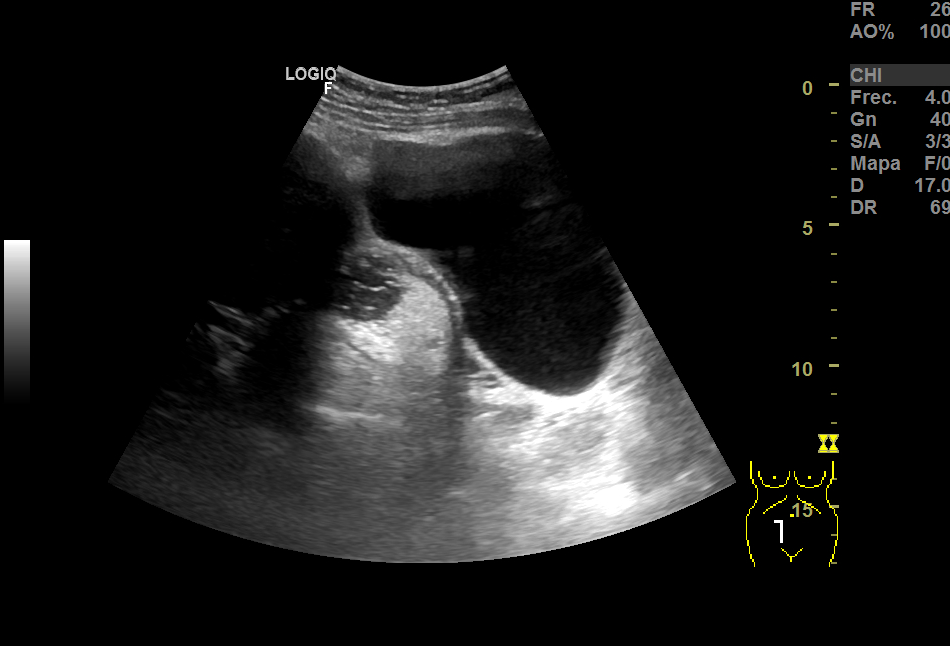

Realizamos una ecografía en el centro de salud y objetivamos, adyacente a útero, una imagen heterogénea de gran tamaño (15x8 cm), con vascularización, que podría corresponder a un mioma gigante. En anejo derecho, imagen redondeada de aproximadamente 3 cm en cuyo interior aparecen líneas hiperecogénicas en un fondo hipoecoico que podrían corresponder a teratoma, sin descartar otra patología. Ante la duda, derivamos a ginecología.

La RMN confirma la masa fibrótica de 11x8x10 en relación con mioma pediculado. Imágenes en la línea medida de fondo saco de Douglas de 55x46 y otra de 37x36, bien delimitadas, hiperintensas, compatibles con teratomas.